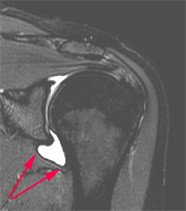

MRI Befund Frozen Shoulder

Das MRI-Bild zeigt einen normalen Befund: Die beiden Pfeile markieren das normale Verteilvolumen des Kontrastmittel im Gelenk